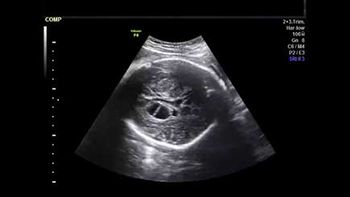

A study in The New England Journal of Medicine funded by the Eunice Kennedy Shriver National Institute of Child Health and Human Development suggests that letrozole may be more effective at helping women with polycystic ovary syndrome (PCOS) become pregnant than clomiphene.